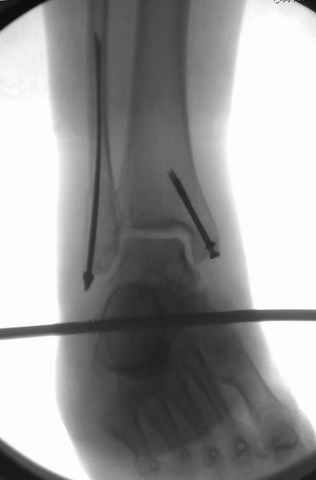

A propos fibular fixation if one is eager to stabilize it separately. In the fracture pattern a way of closed fixation by V-shaped stressed wire (advanced by colleagues from Moscow, prof. Lazarev A.F. et al.) must be excellent. We use indirect closed reduction by the external fixator. Example attached, that fibular fracture is even more suitable for plating but the wire did the job.

Еще, кстати, о фиксации лодыжки, если уж непременно хочется ее отдельно стабилизировать - при таком характере перелома замечательно должен сработать предложенный проф. Лазаревым с соратниками способ фиксации напряженной V-образной спицей. Опять же, открытая репозиция не нужна, мы делаем непрямую репозицию именно аппаратом. В приложении пример, там перелом малоберцовой куда менее поперечный, чем в данном случае, но все равно получилось закрыто без пластинки.